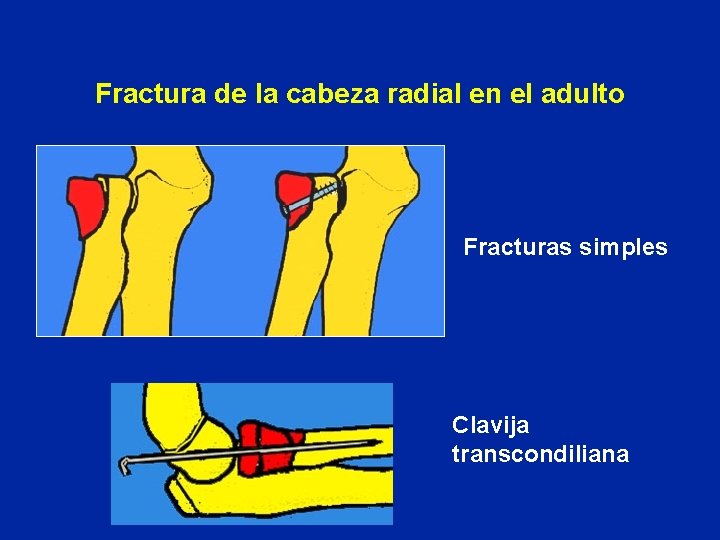

Fractura de la cabeza radial en el adulto Fracturas simples Clavija transcondiliana

Fractura de la cabeza radial en el adulto Fracturas conminutas

Fractura de la cabeza radial